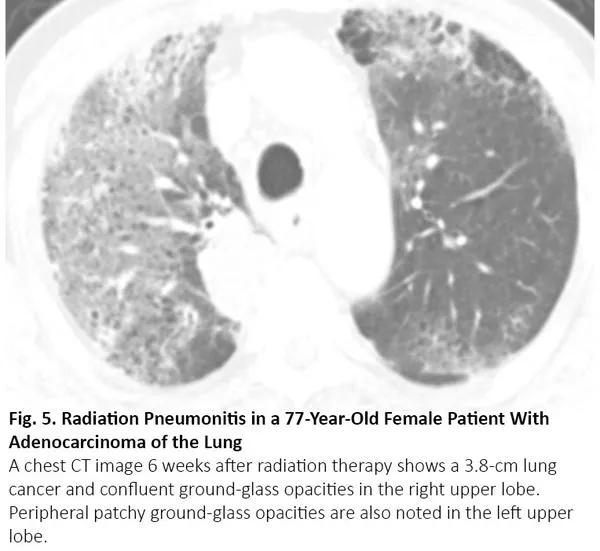

化疗、免疫治疗可引起药物性肺炎,导致CT呈现间质性肺部疾病的影像学表现。12最常见的类型是隐源性机化肺炎,其次是非特异性间质性肺炎、超敏性肺炎和急性间质性肺炎。13其中,隐源性机化肺炎、非特异性间质性肺炎的影像学表现可与COVID-19肺炎相似(图4),反之亦然。14

图4. 一位71岁肺鳞癌男性患者出现纳武利尤单抗治疗导致的肺炎